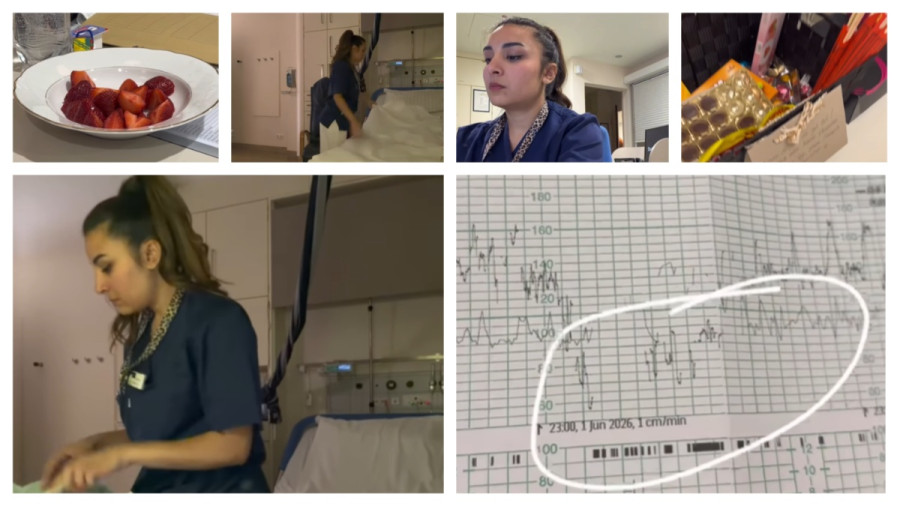

Tokom trudnoće telo prolazi kroz velike promene, a jedna od najvažnijih je povećanje količine tečnosti i krvi. Zapravo, količina tečnosti u organizmu može porasti i do nekoliko litara, dok se zapremina krvi povećava i do 50%. Sve to ima svrhu, od podrške rastu do razvoja bebe, ali istovremeno dovodi do zadržavanja tečnosti u tkivima, što uzrokuje oticanje, najčešće na nogama, ali i na šakama i prstima.

Dodatni razlog za oticanje leži u pritisku koji rastuća materica vrši na krvne sudove, čime se otežava normalna cirkulacija i povrat krvi ka srcu. Hormonalne promene takođe usporavaju izlučivanje soli i tečnosti, pa se višak lakše zadržava u organizmu.

Zbog svega toga, prsti mogu postati otečeni, zategnuti i osetljivi, a nakit – posebno prstenje – može početi da steže. Ono što je juče bilo komotno, danas može postati problem koji ne možete lako rešiti.

Važno je naglasiti da je oticanje u trudnoći u većini slučajeva normalno i očekivano, naročito u kasnijim mesecima. Ipak, postoje situacije kada zahteva dodatnu pažnju. Ako otok nastane naglo, ako je praćen bolom, crvenilom ili se javlja samo na jednoj strani tela, potrebno je obratiti se lekaru, jer to može ukazivati na ozbiljnija stanja poput preeklampsije ili problema sa cirkulacijom.

Da biste smanjile oticanje i sprečile probleme sa prstenjem, preporučuje se da izbegavate dugotrajno stajanje, unos previše soli, kao i boravak na visokim temperaturama. Redovno kretanje, unos dovoljno vode i podizanje ruku i nogu tokom odmora mogu pomoći cirkulaciji i smanjiti zadržavanje tečnosti.